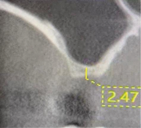

Three months later, a cone-beam computed tomography (CBCT) scan revealed the indication of a MSA due to a pneumatized right maxillary sinus with residual bone height of 2.5 mm and two Underwood septa (Figure 2). Prior to the MSA procedure, based on scientific protocols that suggest smoking cessation for at least 10 days before and after surgery,6,11 the patient was strongly advised to cease his smoking habits due to the risk of bone graft failure.

Fig 2. Preoperative CBCT scan showing a sagittal section of pneumatized right maxillary sinus in edentulous site No. 3.

Figure 2